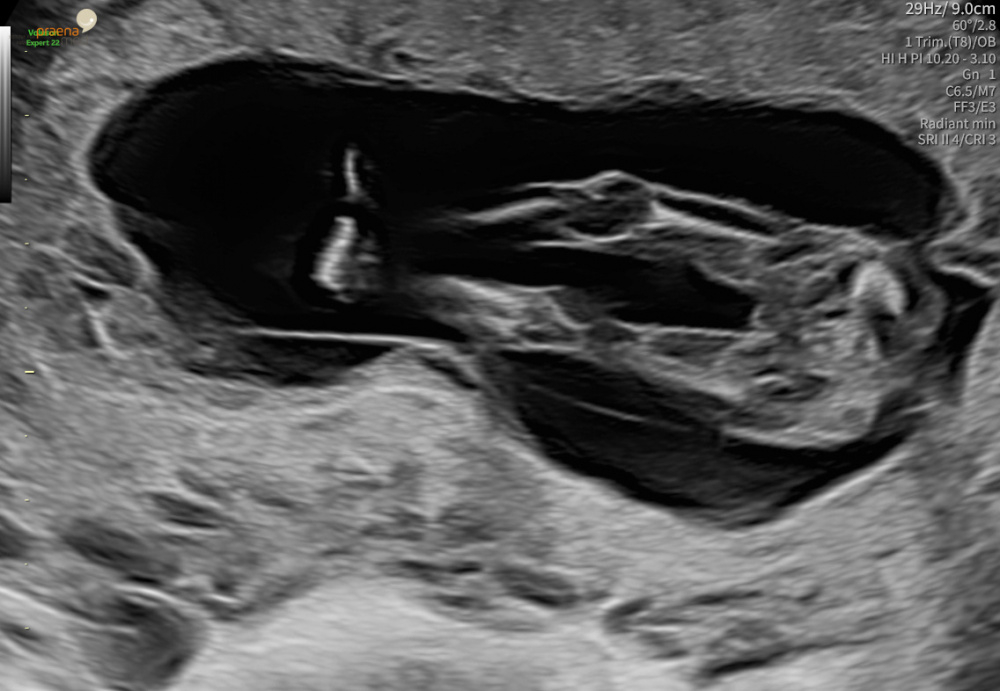

Bei uns sieht es so aus und ich bin wirklich über jeden Tipp dankbar. Was denkt ihr? Leider wollte sich das Mäuschen nicht drehen also schaut ihr sozusagen von oben auf das Baby. Team 🩷 oder Team 🩵?

@sanaao Also für mich wirkt der Nub (sofern er es ist) bissi aufgerichtet, was ja eher für einen Buben sprechen würde, aber ja ein größeres, genaueres Bild würde vielleicht mehr Aufschluss geben ;-)

Ich hätt bei @sanaao auch auf einen Buben getippt. Sieht aus als wär auf dem Nub wie verschwommen noch was drauf, das deutet oft auch auf Buben hin. Als wär da noch ein verstecktes Zipferl …